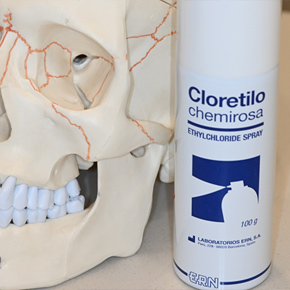

냉각 스프레이

순간적으로 표면 온도를 떨어트려 일시적으로 통증 해소 시켜 줍니다.